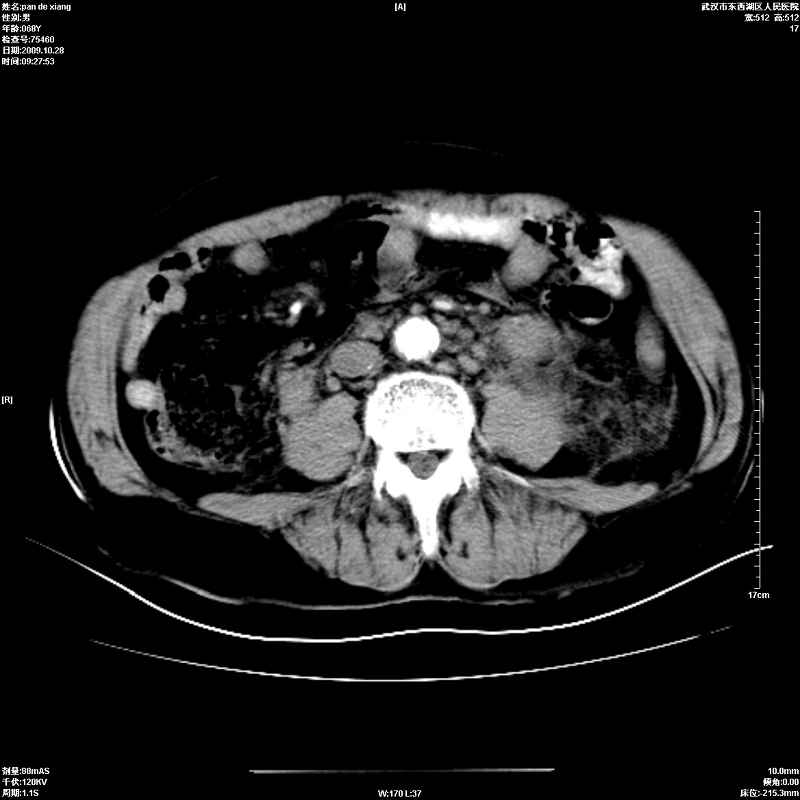

以下是引用杀毒软件在2009-10-28 20:41:00的发言:[br]结合临床考虑---白血病双肾改变或淋巴瘤。

以下是引用zxl51642在2009-10-29 9:59:00的发言:[br]结合临床“单克隆免疫球蛋白血症”,考虑双肾为继发损害并肾功能不全(尿中大量igg及少量iga、igm等大分子免疫球蛋白滤出所致继发损害),椎前软组织肿块为髓外造血。与浆细胞瘤有区别,平扫时有战友说的很清楚。